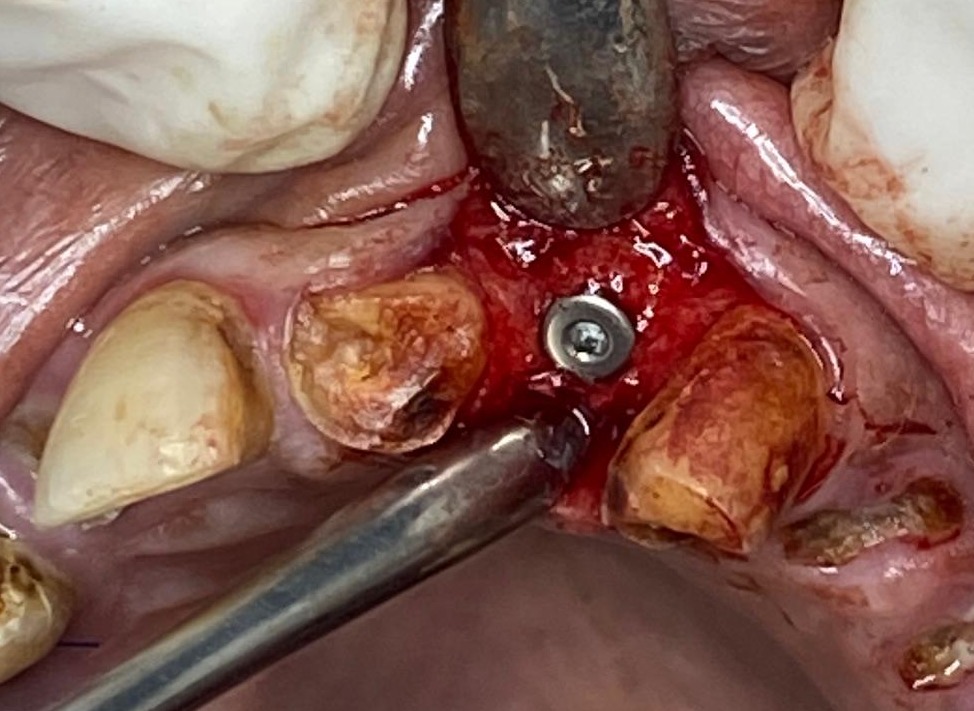

CASE BY DR. SMIJAL --IMPLANT INSERTION IN IDEAL INCISAL EDGE POSITION

IMPLANT inserted for prosthetically driven position which will give excellent aesthetic results.

CASE BY DR. SMIJAL --IMPLANT

IMPLANT placed with 40 NCm  torque.